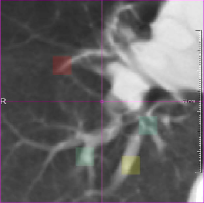

Muenzing et al. [2014] generated an uncertainty map by spatial interpolation of landmark-based quality estimates. On the contrary, our proposed system, which is trained on landmark locations, can be applied in all regions of the image. We showed this for two example images, see Fig. 5. It can be easily visualized that in the blue region, images are matched correctly. On the other hand, by tracking the vessels in the red region misalignment can be seen. Another note about the prediction is that there are no abrupt changes, and error varies smoothly from blue to yellow and then red, even though the error is predicted for each voxel independently.

Another example is given in Fig. 10(a-d). Although all landmarks indicate that the registration error is small in this slice, the quantitative results found several misregistered regions, which implies that few landmarks may not be sufficient to assess the registration quality of the whole image. In Fig. 10(e, f), it can be observed that the performance in the homogeneous area (left side of the images) is as good as the performance in the area with structure. The main reason of acceptable performance in the homogeneous area is that the training samples consist of landmarks as well as their neighborhood region, which can be homogeneous. Thus, the system is trained both for homogeneous regions and regions with structure.

Another example is given in Fig 10(g, h), where the proposed system is not able to predict the registration error correctly because of a shift in the slice direction.

Refer to caption

() Sample 1: IFsubscript𝐼𝐹{I}_{F}

(a) Sample 1: IM(𝐓b)subscript𝐼𝑀superscript𝐓b{I}_{M}(\bf{T^{\mathrm{b}}})

(b) Magnification of (a)

(c) Magnification of (b)

(d) Sample 2: IFsubscript𝐼𝐹{I}_{F}

(e) Sample 2: IM(𝐓b)subscript𝐼𝑀superscript𝐓b{I}_{M}(\bf{T^{\mathrm{b}}})

(f) Sample 3: IFsubscript𝐼𝐹{I}_{F}

(g) Sample 3: IM(𝐓b)subscript𝐼𝑀superscript𝐓b{I}_{M}(\bf{T^{\mathrm{b}}})

Figure 10: Several samples from the SPREAD dataset. The left column shows the fixed image with the ground truth registration error overlaid in color. The right column shows the moving image after registration with the registration error predicted by the proposed method overlaid in color.